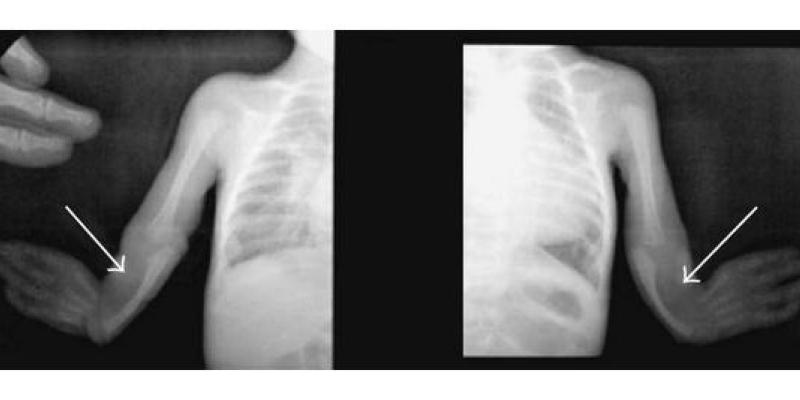

El Síndrome de Baller-Gerold se asocia a la craneosinostosis coronal, además de aparición de anomalías del eje radial, como son la oligodactilia, aplasia o hipoplasia del pulgar, aplasia o hipoplasia de radio.

Además, si se presentan otras malformaciones como las nombradas, y si es necesario, se puede realizar la pulgarización del dedo índice para la reconstrucción del dedo pulgar, que es inexistente para este tipo de síndrome.